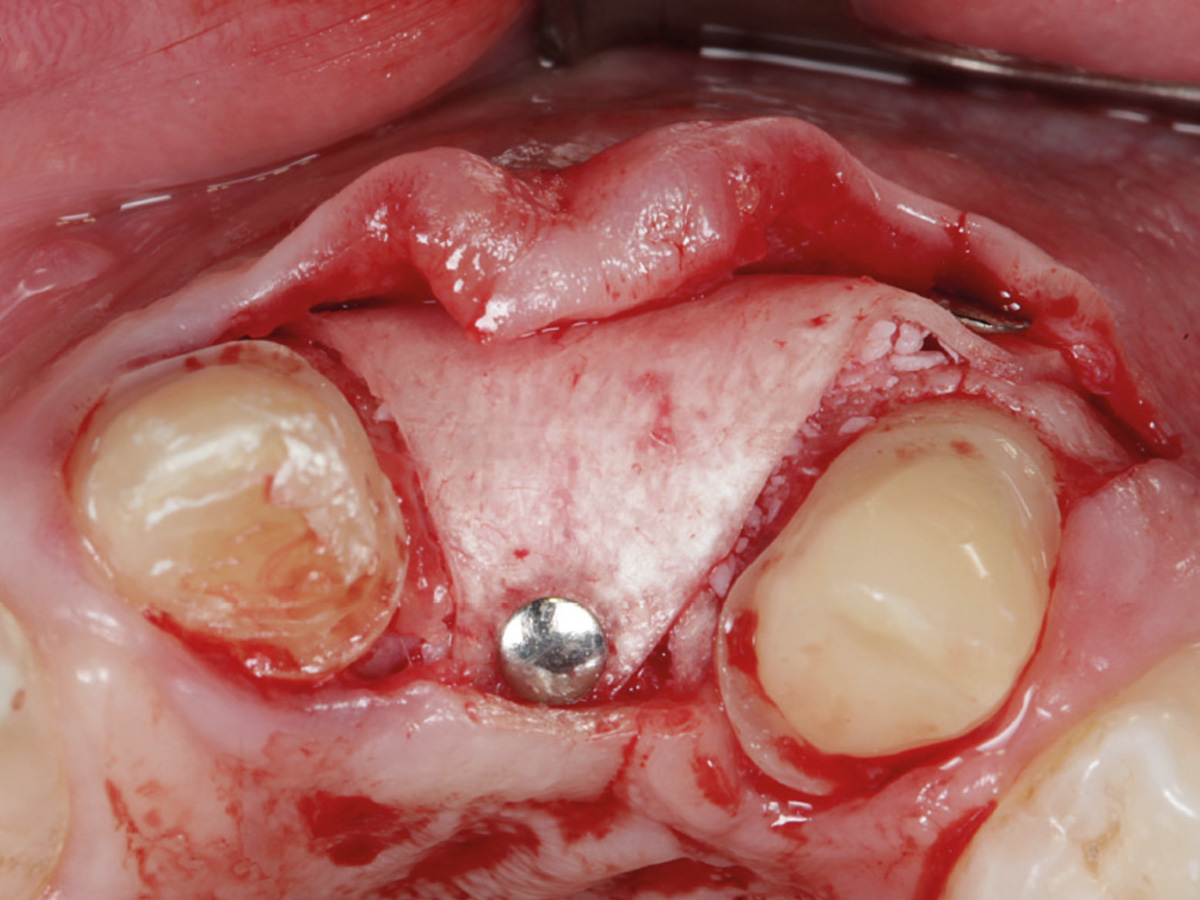

Abbildung 3

Nach Bildung eines Mukoperiostlappens wird mit der Bone Lamina die bukkale Lamelle rekonstruiert. Die Lamina wird mit Titanpins befestigt.

Abbildung 4

Der Defekt wird mit mp3® augmentiert.